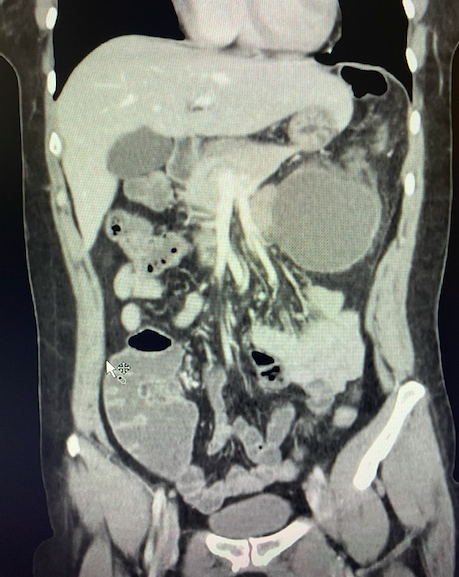

Se realiza ecografía clínica donde se objetiva una colección hipoecoica a nivel de ángulo esplénico del colon. Se escala analgesia administrando Fentanilo 75 mcg y Metoclopramida 10 mg y se traslada al Hospital de referencia. Se realiza escáner de urgencia: colección de contenido hipodenso de 72mm x 55mm x 70mm, en íntimo contacto con ángulo esplénico del colon, que presenta alteración inflamatoria de la grasa adyacente. Se decide ingreso en Cirugía General y de Digestivo.

Colección abdominal a estudio.